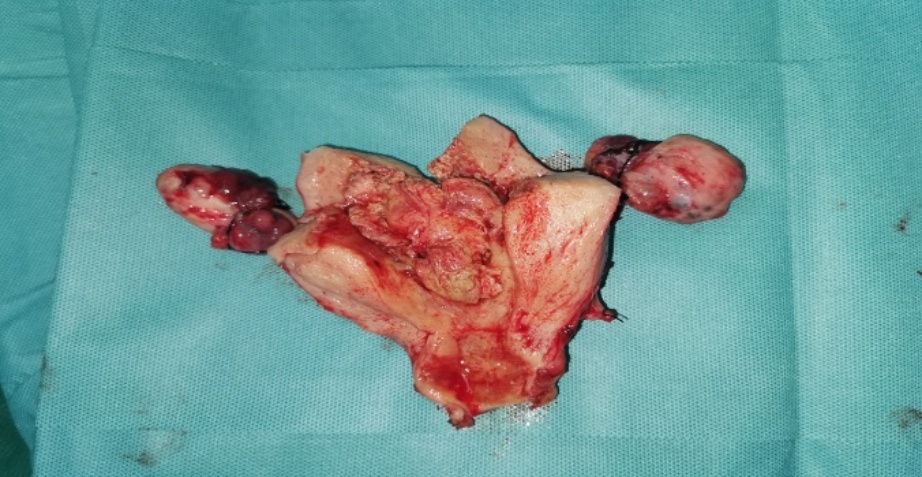

根据患者症状、体征及辅助检查,该患者入院诊断为:盆腔肿物性质待诊:卵巢肿瘤可能,子宫肌瘤,人乳头瘤病毒感染,腹水,左侧乳腺全切术后。患者现盆腔肿块性质不明,考虑卵巢癌可能性大,手术指征具备。已完善相关辅助检查,排除手术禁忌,遂在全麻下行经腹筋膜外全子宫切除术加双侧附件切除术加大网膜切除术,术中见:盆腔内淡黄色腹水约1000 ml,子宫增大,表面充血,下段与膀胱致密粘连,见多个肌瘤突起大者位于宫颈左侧壁,直径约8 cm,宫颈右前壁见直径约3 cm肌瘤,左侧卵巢增大,见大小约6 × 5 × 4 cm实性肿瘤,右侧卵巢见大小约16 × 12 × 12 cm肿瘤,双侧输卵管未见明显异常(图1(c)图1(d)),肝胆胰脾、胃肠表面未见明显异常,大网膜局部增厚,未见明显挛缩。术中冰冻病理示:((1) 左侧附件;(2) 右侧附件)双侧卵巢均见异型细胞列兵样排列,结合病史,意见为癌,首先考虑转移性癌,高度怀疑乳腺浸润性小叶癌转移。手术顺利。

(c) (d)